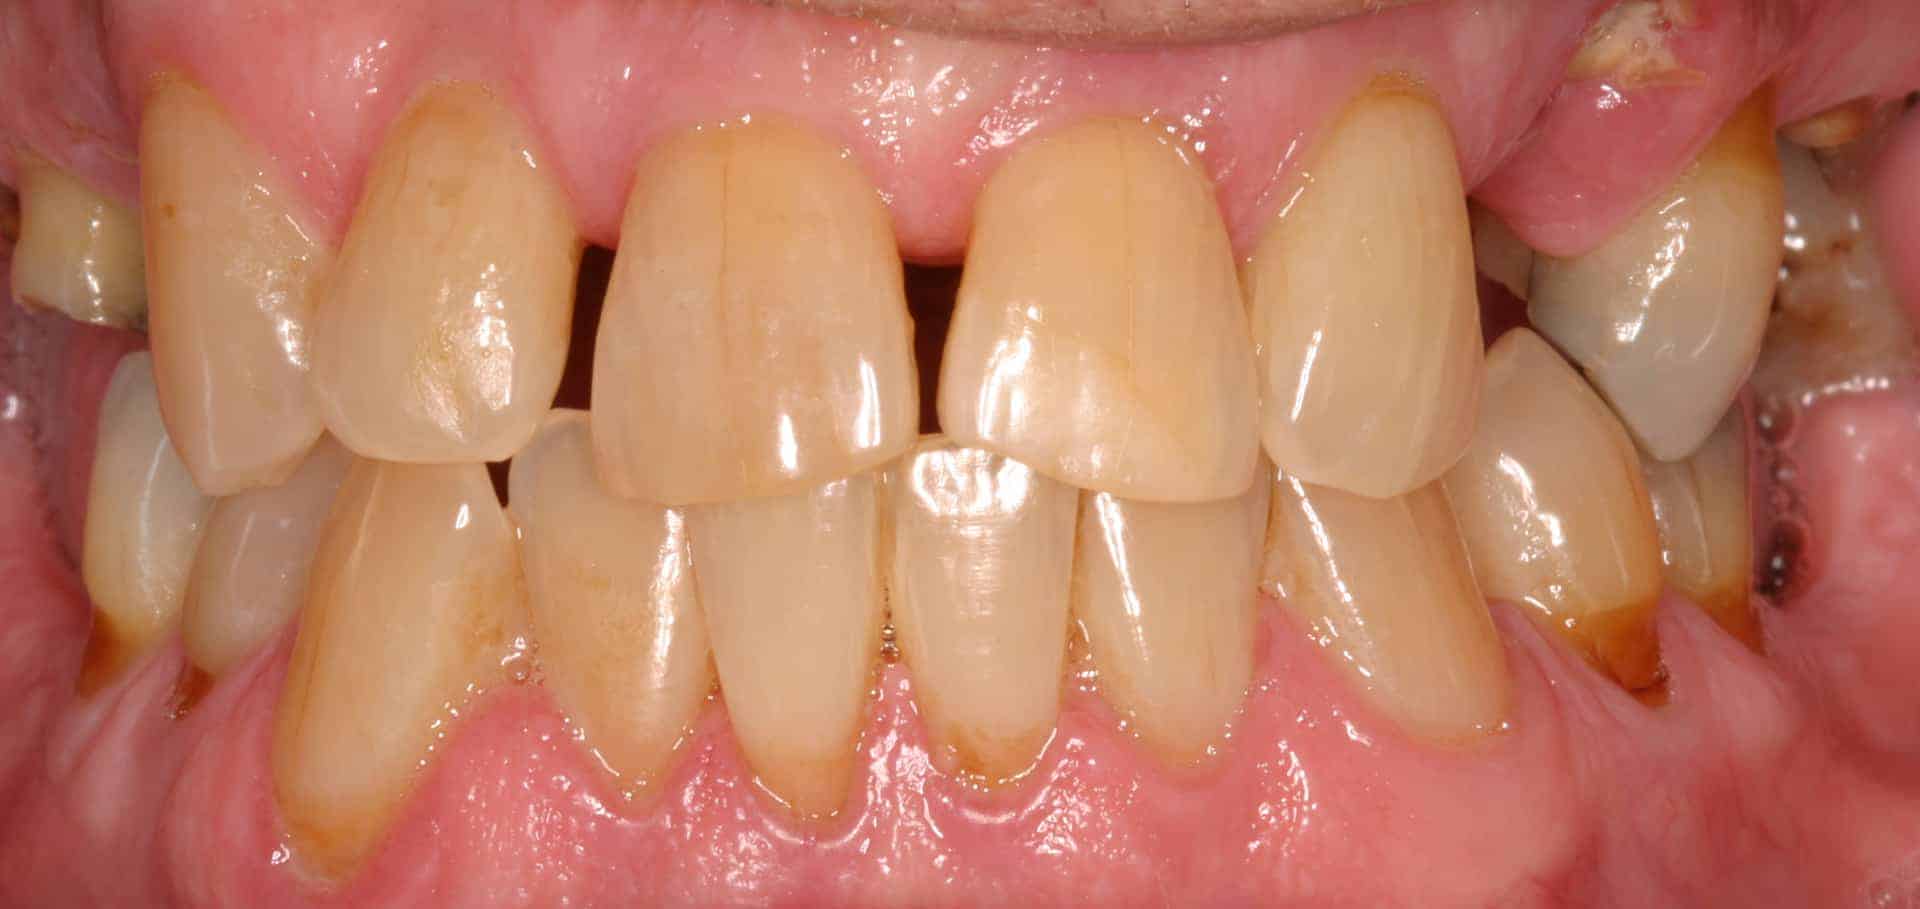

Before: Failed upper remaining teeth requiring removal. Patient elected to proceed with Phase I immediate complete denture therapy with the view toward phase II implant therapy.